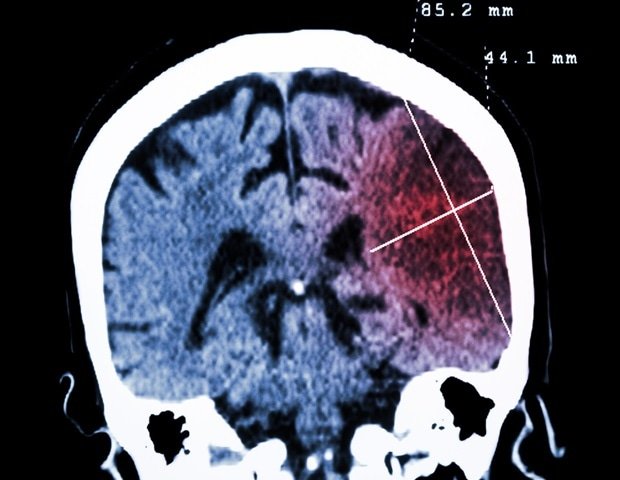

Kleeman’s team focused on anti-NMDA receptor encephalitis (ANRE), a debilitating autoimmune brain disease popularized by Susannah Cahalan. new york times bestseller brain on fire. In ANRE, the immune system attacks proteins in the brain called NMDA receptors, causing psychosis, insomnia, and seizures. It turns out that many patients with this condition have tumors outside their brains that produce the same NMDA receptors.

Using mouse models of breast cancer, the researchers tracked antibodies as they evolved from precursors present at birth into potent cancer-killing molecules within tumors. Mice with the strongest antibody responses were observed to have spontaneous tumor shrinkage. However, when the same antibody was injected into the brains of healthy mice, it triggered seizures and increased body temperature, similar to what ANRE patients experience.

An important advance was made by Professor Hiroshi Furukawa of CSHL, an expert in molecular neuroscience. Using a method called cryo-EM, he noticed that some antibodies activated NMDA receptors, while others inhibited them.